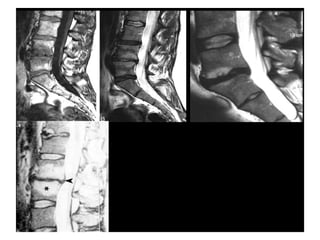

Modic type 3 degenerative changes

(MIII)

Hypointense on both

T1WI (A) and T2WI (B)

Type III changes

(Lack of signal)

• Correlate with extensive

bony sclerosis on plain

radiographs.

• Reflects the relative

absence of marrow in

areas of advanced

sclerosis

• Considering the

histology;

– dense woven bone within

the vertebral body

Modic Type III

(Sclerosis)

are presumably bone sclerosis